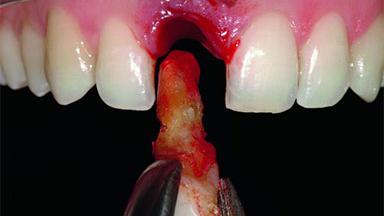

A 32-year-old female Caucasian patient with a compromised maxillary right central incisor was referred to us by a general dentist. Her chief complaints were discomfort and mobility of tooth 11 with unsatisfactory esthetics due to discoloration. The patient reported a previous trauma, some years earlier, as the origin of pathology on the afflicted tooth. Anamnesis was negative for any other dental or periodontal pathology in the remaining dentition. The patient did not take any medication and reported to be a light smoker (5–10 cigs/day). She had high esthetic expectations of her treatment. The extraoral examination revealed a high smile line with full exposure of her maxillary teeth and surrounding soft tissue in the area between the second premolars.

Bone Volume Deficient horizontally, requiring prior grafting